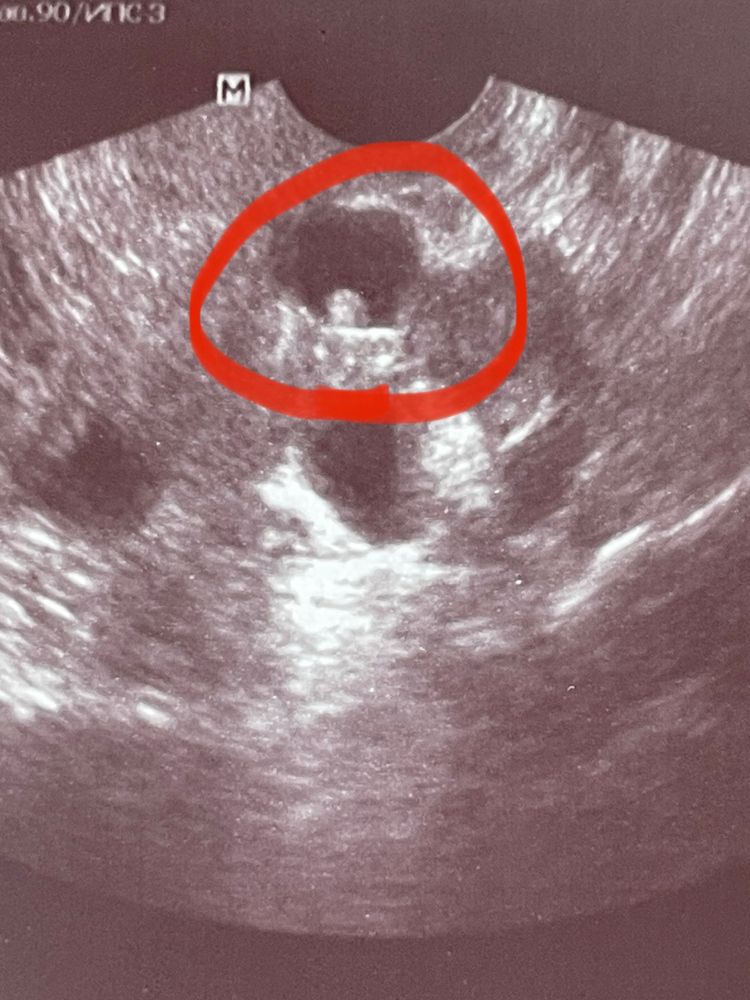

Что на снимке УЗИ?

Киста с пристеночный компонентом. Точно не беременность, потому что образование не в полости и даже близко не к полости, а в миометрии, во-вторых есть аналогичные кисточки, в третьих хгч был бы положительный, пока существует плодное яйцо. Лапара и гистера будут малоинформативны. Сделайте мрт органов малого таза. Я за эндометриоз/аденомиоз такой. Узловые формы бывают

Sofia, о беременности речи не идет, не о маточной не о внематочной. У Вас скорое всего овуляции не было в этом цикле. У Вас кисты обоих яичников, и киста внутреннего слоя матки, что и представлено на фото. Но киста имеет включение внутри, это не эмбрион. Все достаточно однозначно. Вам надо обратится к гинекологу для лечения кистозных изменений яичников и этой кисты.

Mari, киста/ эндометриома/ внематочная 3 разных врача